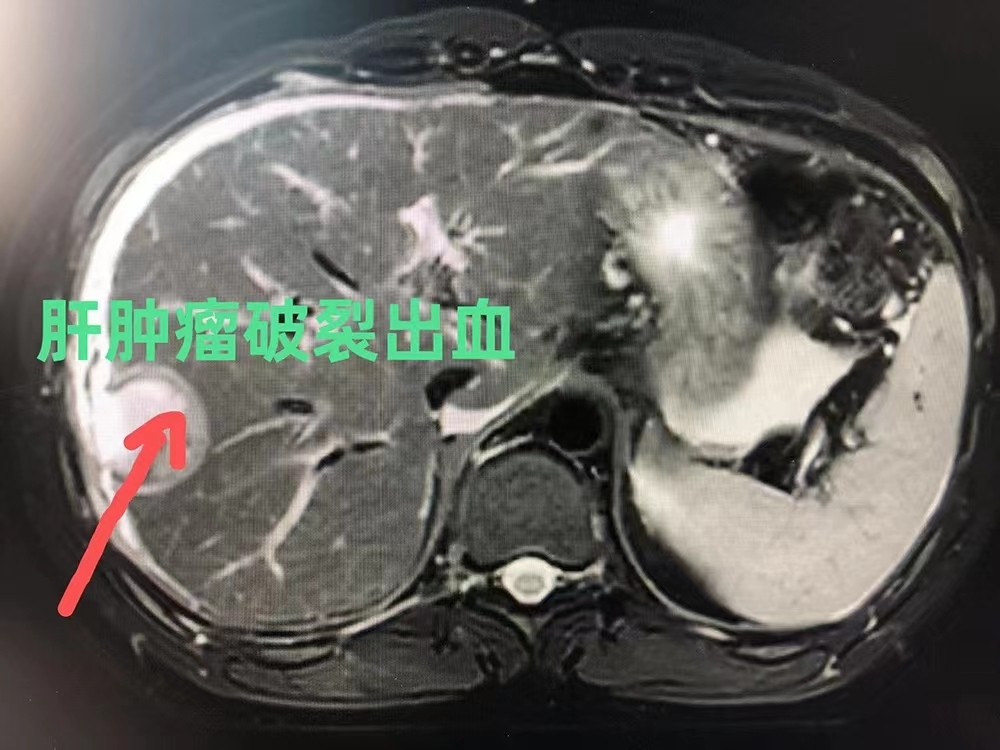

患者男性,40岁,因“腹痛乏力2小时”急诊入院,腹部MRI检查发现:右肝占位,大小为3×3cm,病灶破裂出血,肝周少量积血,诊断为原发性肝癌破裂出血。我院副院长弋鹏圣博士立即组织肝胆外科及麻醉科相关人员进行讨论,在充分评估病情后,弋鹏圣博士决定急诊为患者行腹腔镜下肝肿瘤切除术。经过严格术前准备,由弋鹏圣博士主刀,肝胆外科、麻醉科、手术室密切配合。术中探查发现肿瘤破裂处仍有活动性出血,手术视野差,显露困难,弋博士和助手迅速控制肝门血供,完全游离右半肝后行腹腔镜下右肝肿瘤切除,手术历时3个小时。术后第二日患者自主下床活动,恢复良好,无术后并发症发生。